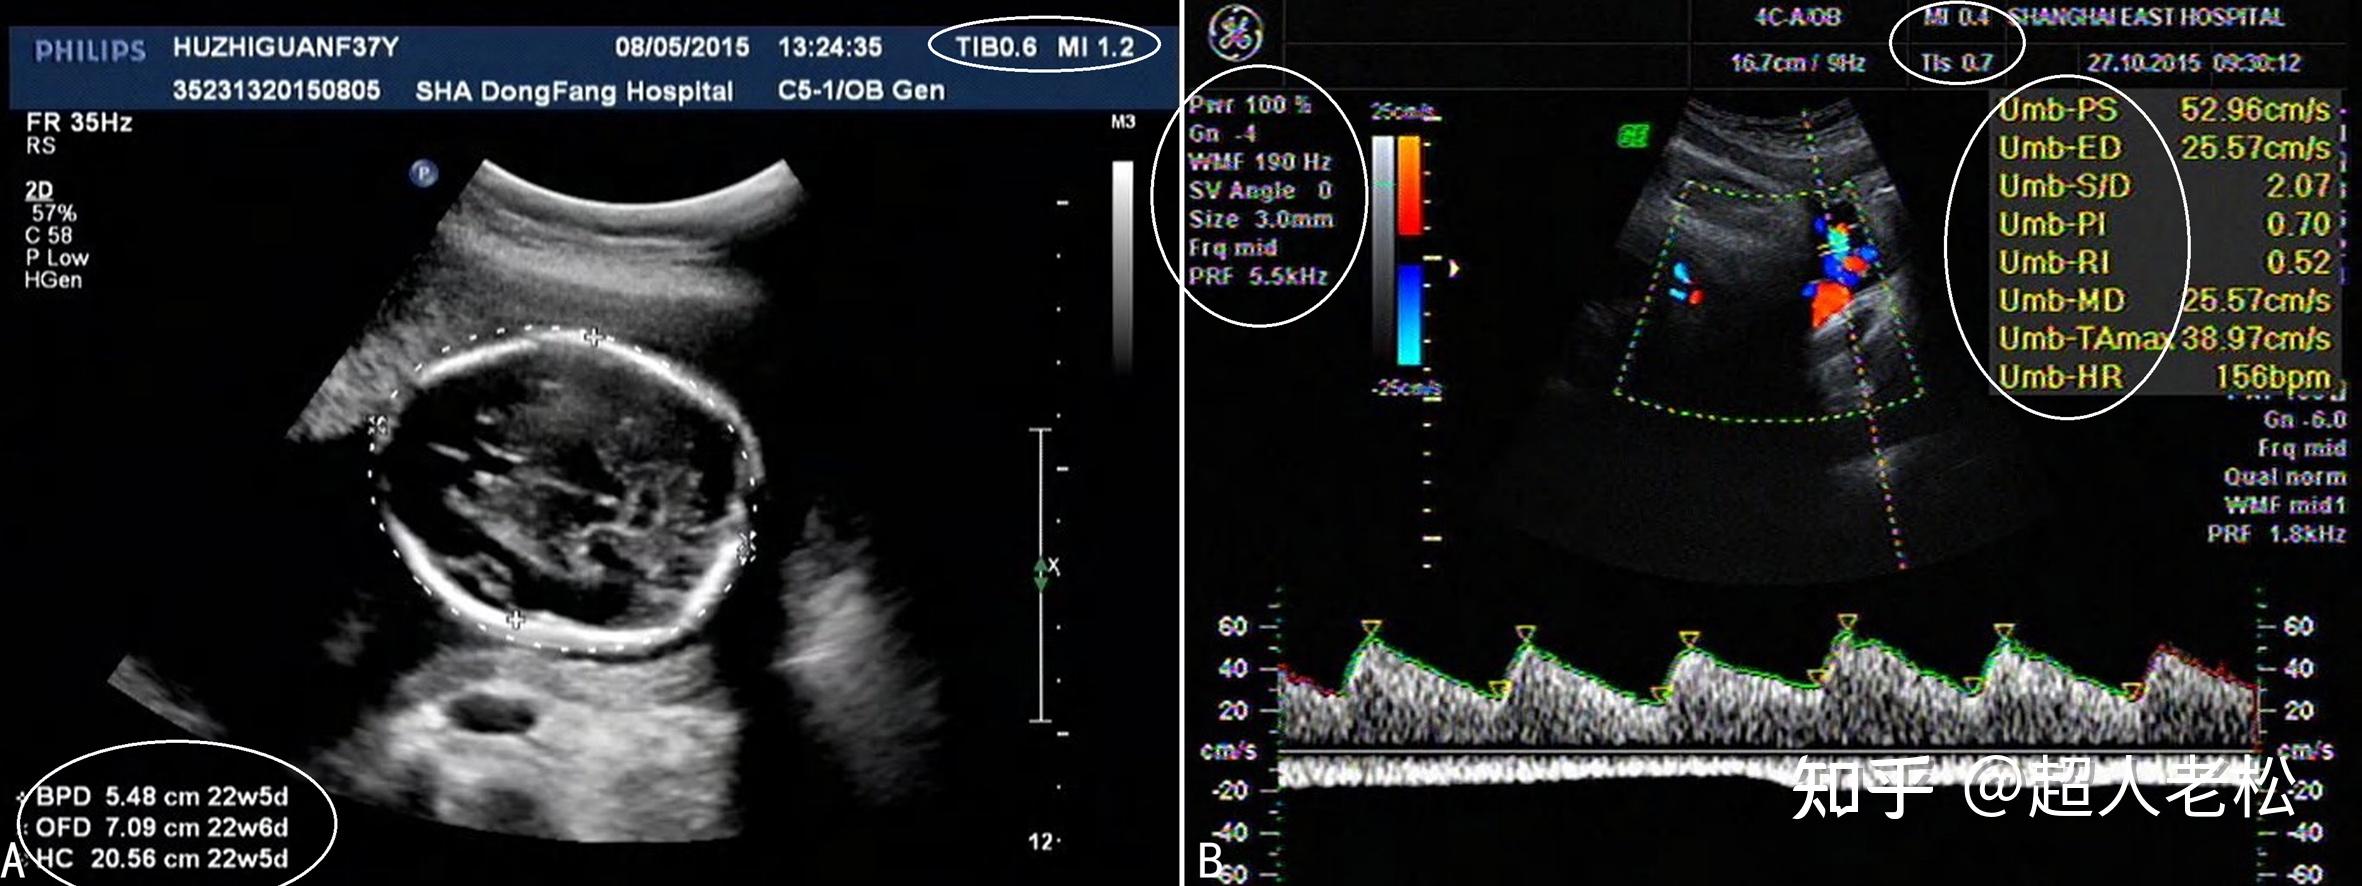

图2-11-8 脉冲多普勒法剑突下切面腹主动脉血流频谱:收缩期为前向血流

图片尺寸365x319